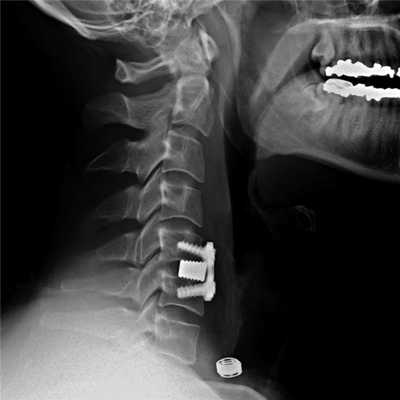

Пациенту был поставлен диагноз: распространенный остеохондроз шейного, грудного и поясничного отделов позвоночника. Дегенеративный стеноз позвоночного канала на уровне С6-С7 справа. Формирующийся артифициальный костно-металлический блок на уровне Th10-L1 после транспедикулярной фиксации. Формирующийся артифициальный костно-металлический блок на уровне L4-L5, L5-S1 после транспедикулярной фиксации и заднего межтелового спондилодеза. Компрессионно-ишемическая радикулопатия С7 справа. Выраженный болевой синдром.

Была проведена операция: тотальная дискэктомия С5-С6, С6-С7, микрохирургическая декомпрессия спинного мозга и его корешков, вентральный межтеловой спондилодез имплантатом из пористого никелида титана.

Послеоперационный период протекал без осложнений. Корешковая симптоматика купирована. Пациент был выписан на амбулаторное лечение у невролога по месту жительства.

Импланты шейного отдела позвоночника на рентгене.